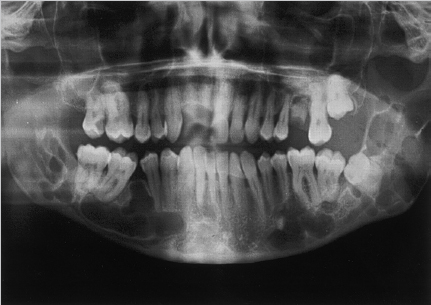

Fig. 3.4). Patients may also have cysts of the skin (steatocystomas) and bone, particularly the mandible (

Fig. 3.5) and maxilla (odontogenic keratocysts).118,123 Also present are skeletal anomalies including spinal and rib deformities, excessive ossification of cranial bones and falx cerebri with concurrent frontal bossing and bridging of the sella turcica.118,123,125 Palmoplantar pits (

The BCNS (NBCCS Gorlin’s syndrome) is a rare, autosomal dominant disorder due to germline mutations of the human patched gene (PTCH). The histologic appearance of the BCCs in BCNS does not differ from those seen in sporadic cases. The diagnosis should be suspected in patients who present with multiple BCCs, especially when these occur at an early age and are located on the trunk. These patients require aggressive approaches to therapy and frequently are disfigured from surgical treatments by the third decade of life. Affected patients have distinct clinical features and predilection for multiple tumors, especially multiple BCCs, usually by age 35.99 Clinical features often include macrocephaly, hypertelorism, bifid ribs, palmar and plantar pitting, osseous cysts (of the mandible), and medulloblastoma (3–5%).99,128

Fig. 3.5 Mandibular cysts of Gorlin’s syndrome. When patients with Gorlin’s syndrome have mandible tumors, they are characterized as keratocystic odontogenic tumors. Above is a Panorex example.